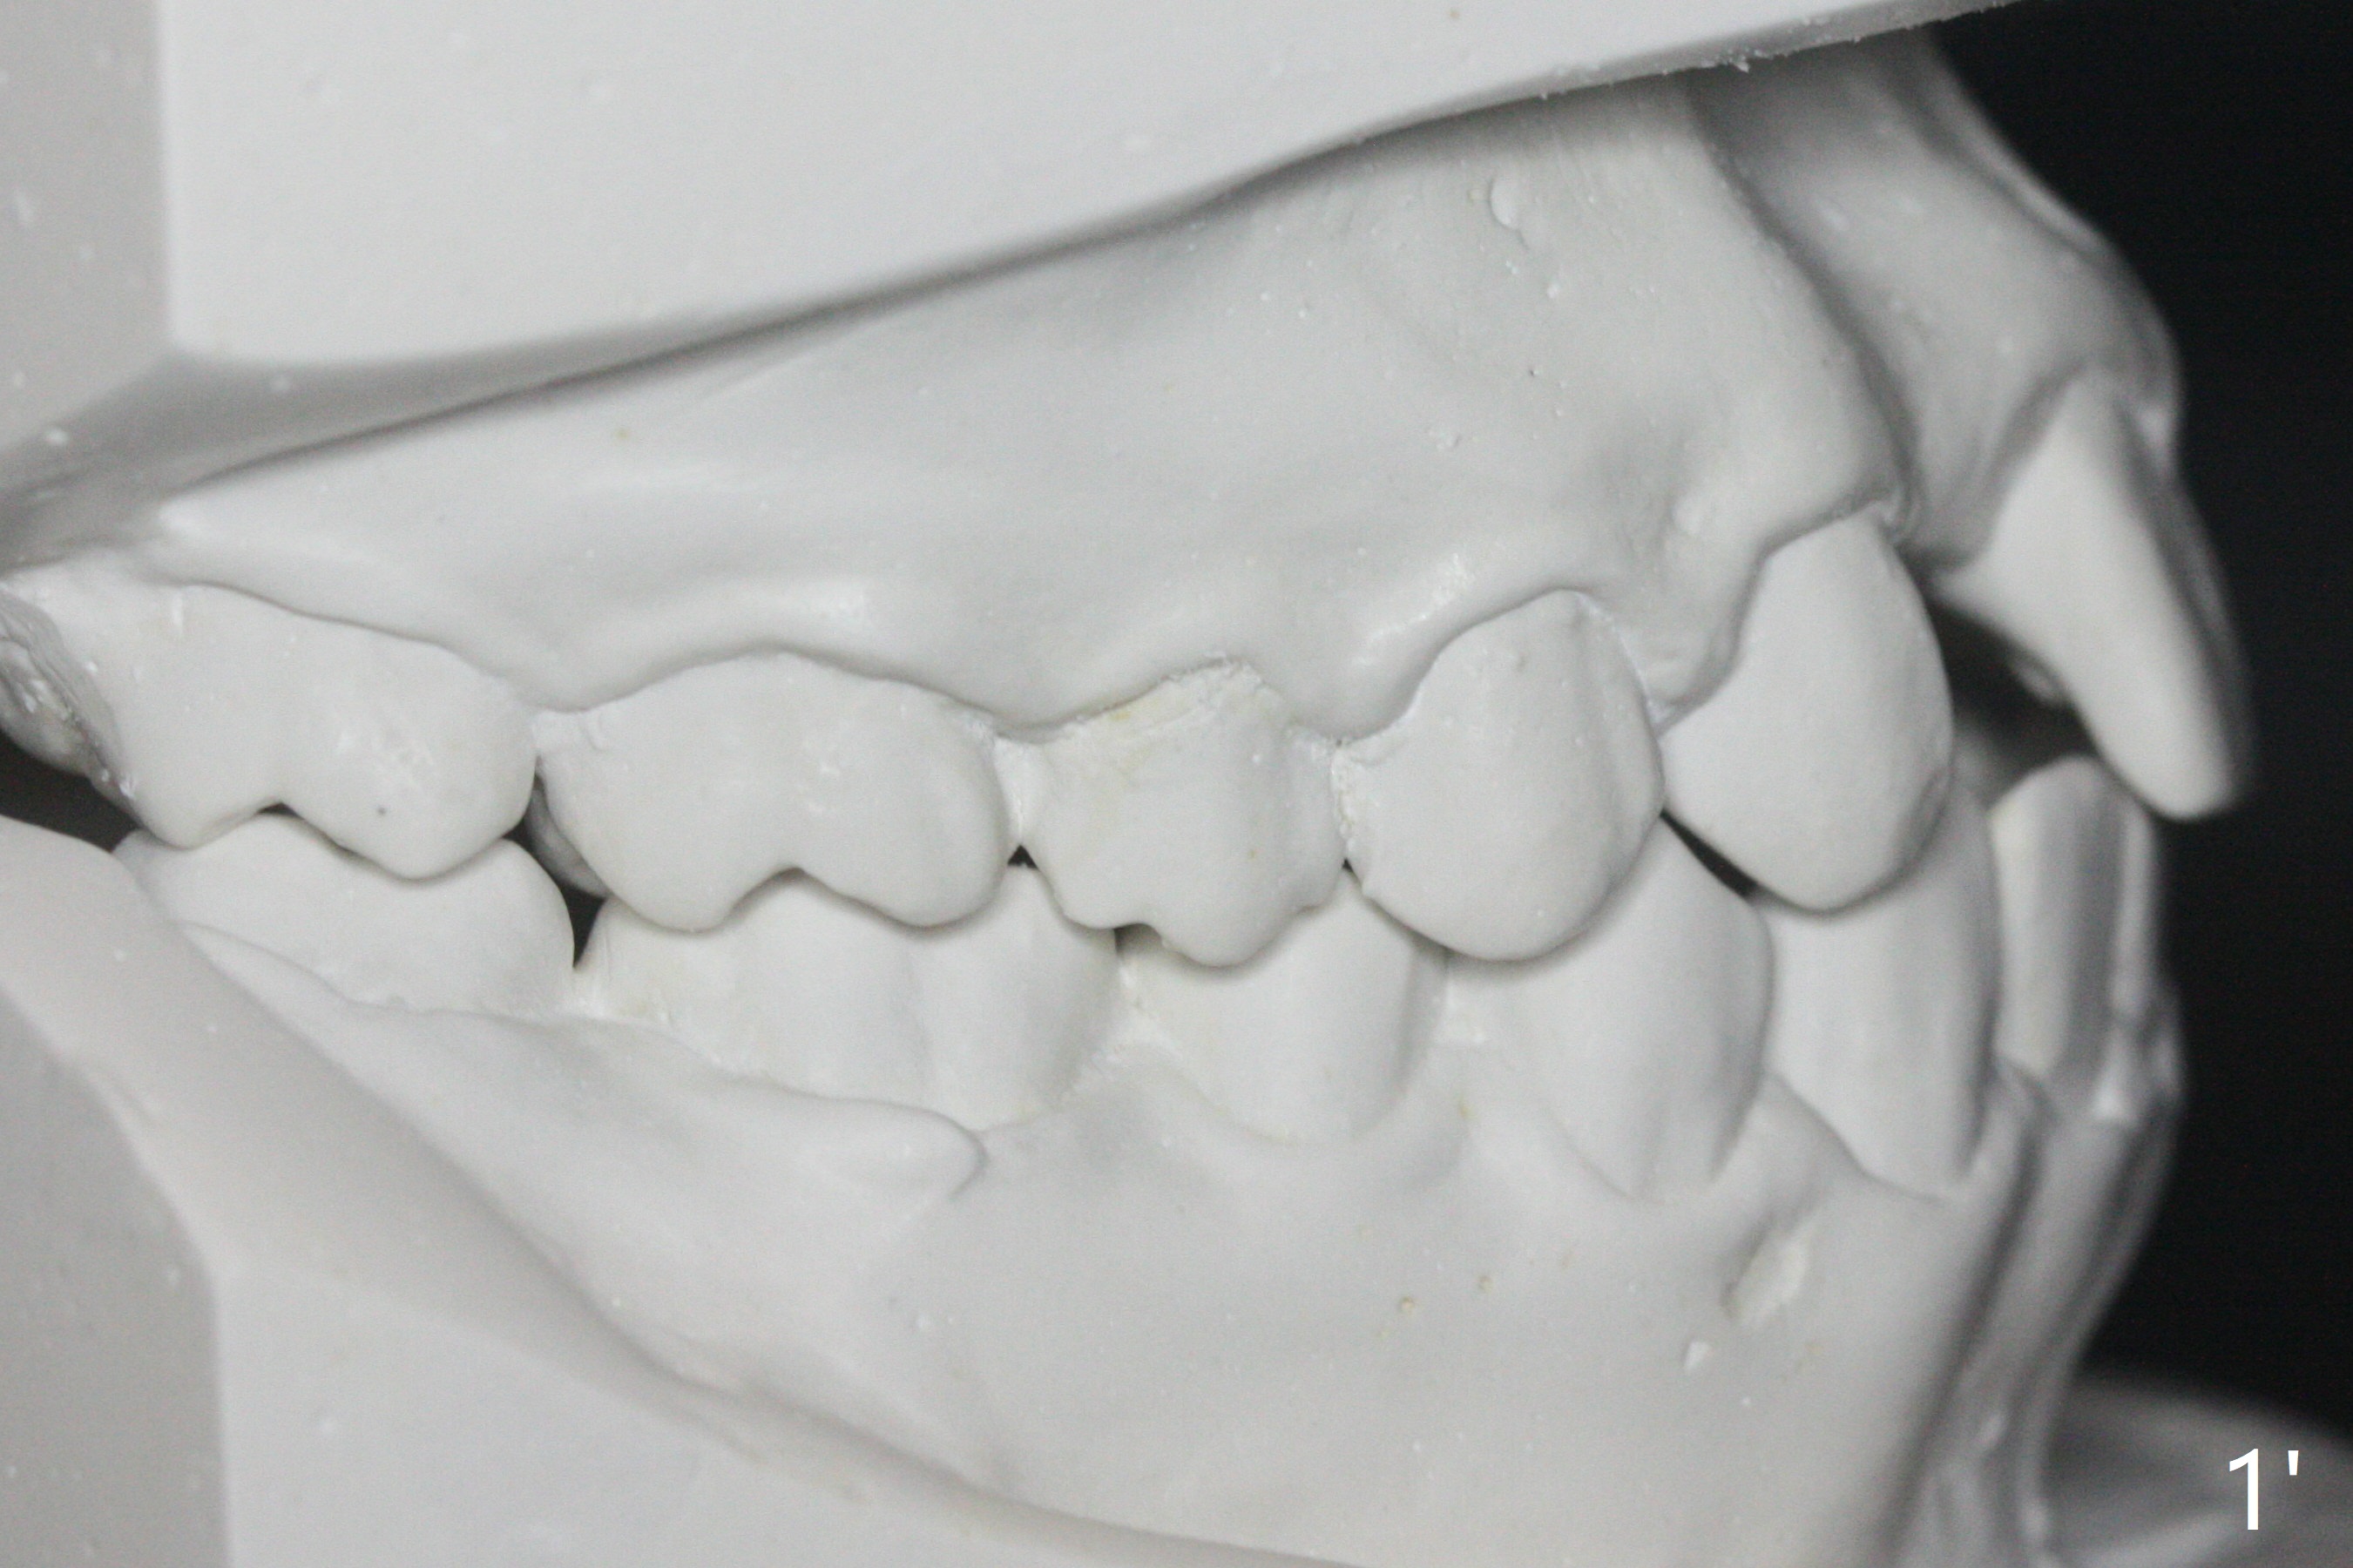

A 15-year-old man finishes orthodontic treatment for congenital missing lateral in 13 months. Molar Class I relationship remains the same (Fig.1,2,4,5). The upper diastemata mesial to 4s (Fig.4,7") close with correction of the upper midline deviation (Fig.2'-4'). The kid is unpleased with the elongated UR1 (Fig.2',3'). In fact it is a preexisting condition (Fig.2 arrow, 2"), but bracket placement at UR1 should have been overcorrected (incisal placement, Fig.3"). The intrusion should be done (Fig.4") before closure of the diastemata, since anchorage may be weakened when the separation between UR1 and 3 increases by using open coil spring. To prevent immediate relapse of the diastema between the upper central incisors, a fixed retainer is placed lingual before debracketing (Fig.6,6',6").